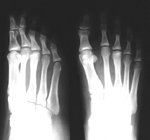

Figure 3 illustrates AP and medial oblique views of a foot revealing Freiberg's disease of the head of the third metatarsal head with very similar radiographic changes as described in figures one and two.